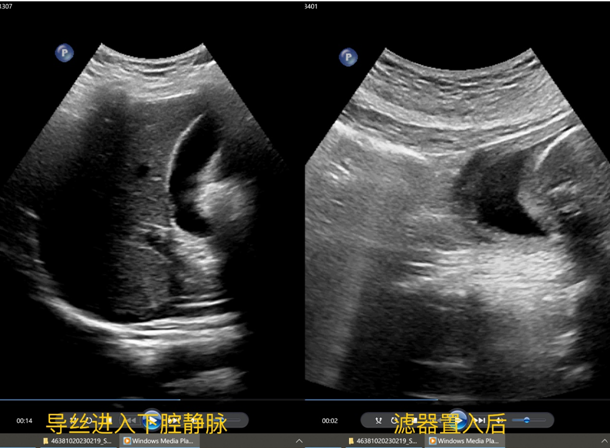

手术过程中,患者取平卧位,右侧腹股沟常规消毒铺巾,2%利多卡因5ml局部麻醉,右侧股静脉穿刺,置入导丝,确认导丝进入下腔静脉,顺导丝置入鞘管,拔出导丝,确认鞘管顶端位于肾静脉水平以下、汇合部以上的下腔静脉腔内,以顶杆推入滤器至鞘管顶端,超声定位,释放滤器,超声观察:滤器打开顺利,位置正常,形态良好,彩色血流示:滤器内血流通畅。

急性下肢深静脉血栓形成是临床常见的外周血管疾病之一,肺栓塞(PE)是下肢深静脉血栓(DVT)常见和严重的并发症,90%以上PE患者伴有下肢DVT,其中20%为症状性或致死性PE。下腔静脉滤器置入是防止下肢静脉血栓脱落、引起肺动脉栓塞的有效方法。下腔静脉滤器置入手术常规在DSA下完成,但对于不宜暴露在射线下(孕妇)、对造影剂过敏、肾功能不全、不能搬动等特殊情况的患者,超声引导下的腔静脉滤器置入术是一种既安全又方便的方法。黑料网开展的此例手术,患者不会接触X线的辐射,全程不需要用到造影剂,医护不需要穿厚重的铅衣,缩短了手术时间,极大提高了手术效率。